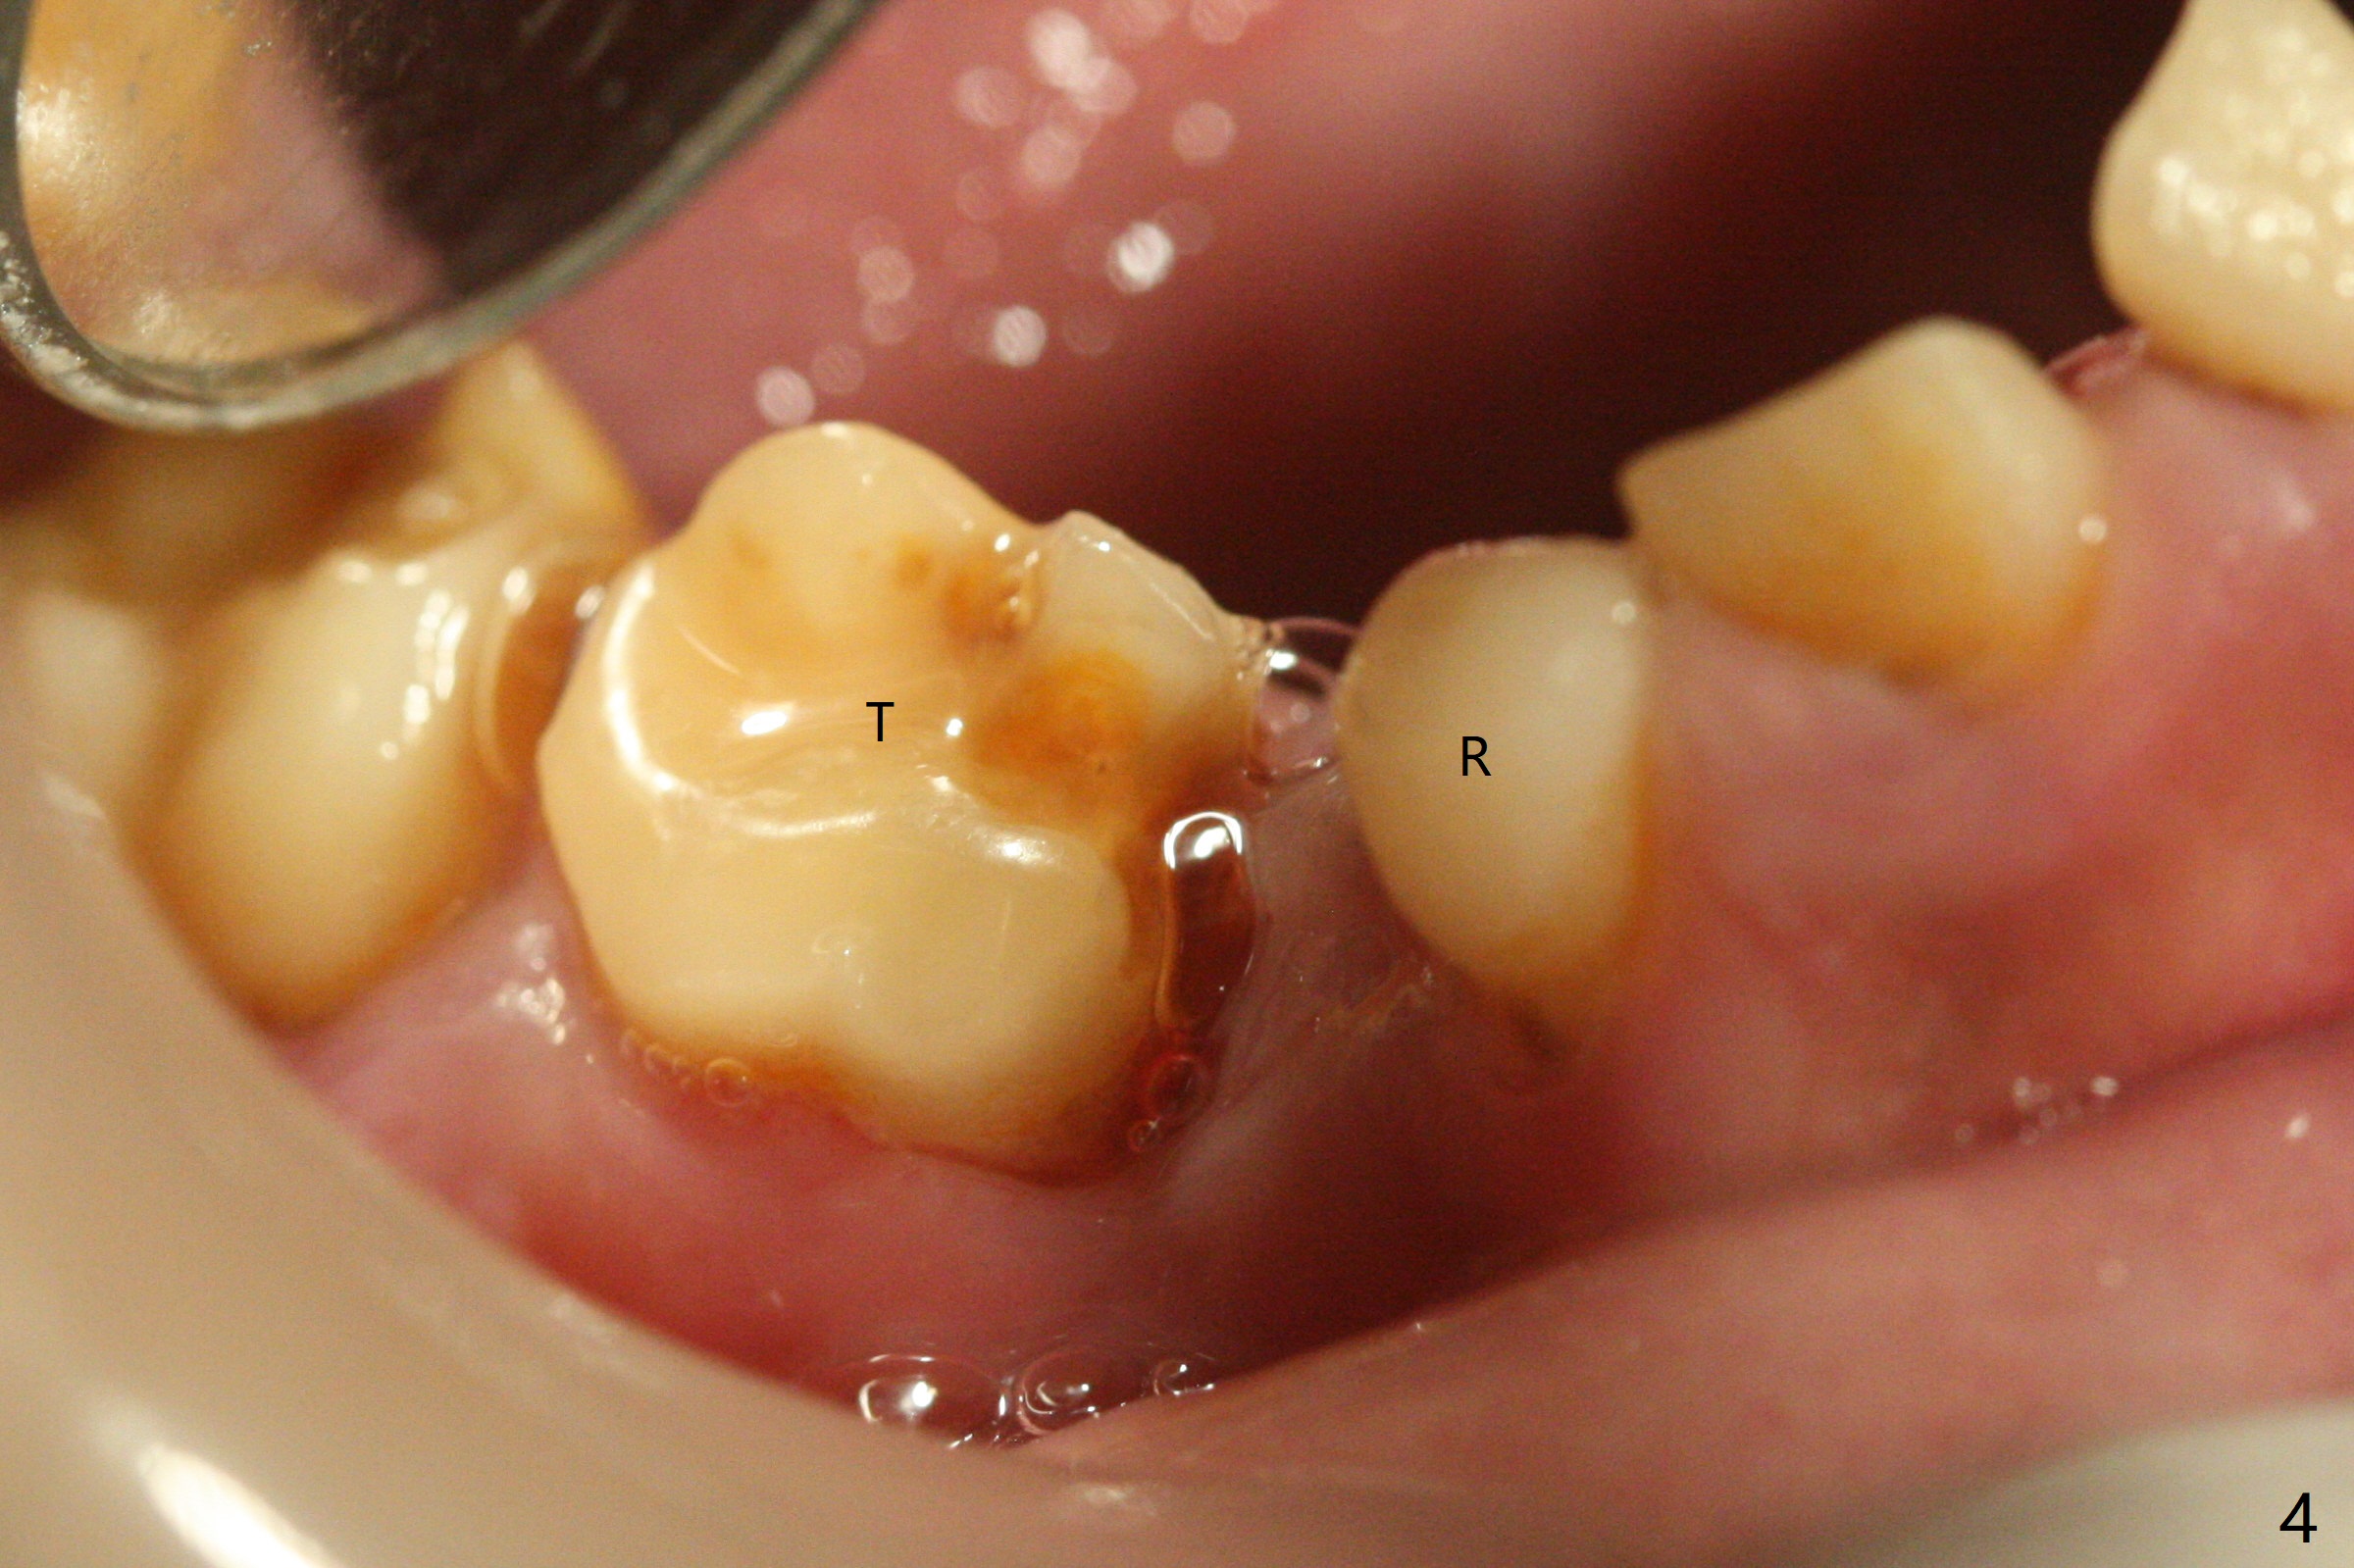

13岁男孩,每颗乳恒牙交换时乳牙都需要拔除,萌出的恒牙个子小,侧切牙反合(图二,五),对冷热敏感,不爱刷牙,口腔卫生欠佳(图三:13(结石)),父母要求诊治。今天在局麻下,左上洁治,没有局麻区域无法洁治,敏感,并且拔除H-J。S下沉,5,28埋伏(图七),其余乳磨牙都有龋齿。如何治疗?是釉质发育不全?暴露5,28前将拍摄CT。